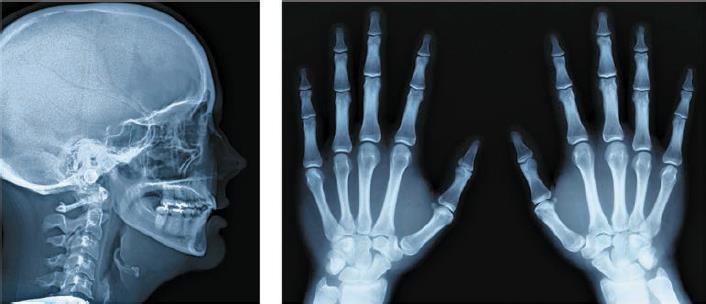

Следующую, ещё более коротковолновую, область электромагнитного спектра называют рентгеновским излучением. Его открыл в 1895 г. немецкий физик Вильгельм Конрад Рентген (1845–1923), обнаружив существование невидимого излучения, которое он назвал Х-лучами. Лучи Рентгена обладают способностью глубоко проникать в предметы и вещества. Благодаря этому их используют для исследования внутреннего строения всевозможных объектов: человеческого тела, кристаллов, древних произведений искусства и многого другого (рис. 85). За своё открытие Рентген был награждён первой в истории Нобелевской премией по физике.

Рис. 85. Рентгеновские снимки